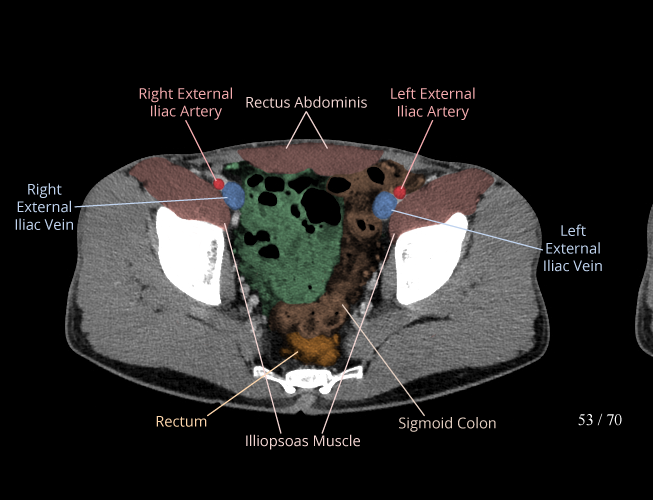

Body

Covers abdominal CT anatomy.